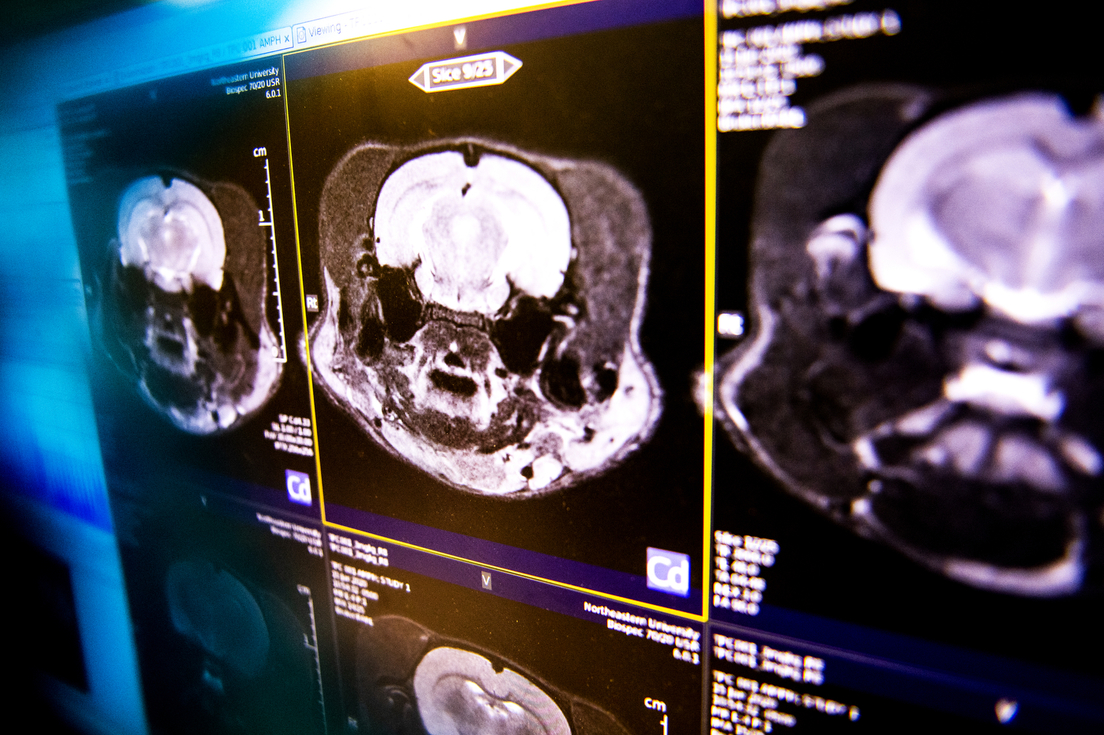

Craig Ferris, profesor de Psicología de dicha universidad, se dio cuenta de la condición única de la rata después de hacerle una resonancia magnética, un procedimiento ordinario para nuevos animales antes de empezar a estudiarlos.

"Cuando miré a la pantalla, vi que la rata, de hecho, no tenía cerebro", ha señalado el científico en declaraciones publicadas por el sitio web de su universidad.

La resonancia reveló que la rata, identificada como 'R222', sufría hidrocefalia severa: su cerebro fue aplanado hasta lucir similar a un panqueque. Lo que quedaba estaba tan deformado que los investigadores al principio no lograban identificar las estructuras del cerebro, aplastado por el líquido cefalorraquídeo. De hecho, lograron encontrar el hipocampo gracias a unos marcadores bioquímicos.